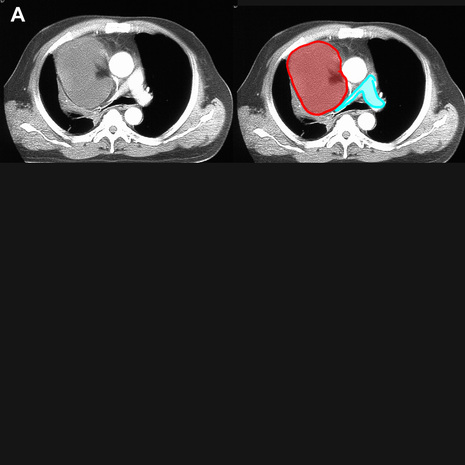

Figure A shows an abnormality of the right pulmonary artery.

The main, right and left pulmonary arteries are outlined in blue. There is a large right mediastinal mass of relatively low attenuation (a liposarcoma) that is compressing the right pulmonary artery.

In this case, a small cell lung carcinoma (outlined in red) has directly invaded the right pulmonary artery  (outlined in purple), producing complete obstruction of flow to the right lung.  Only bronchial artery branches remain patent to supply blood to the right lung tissues.